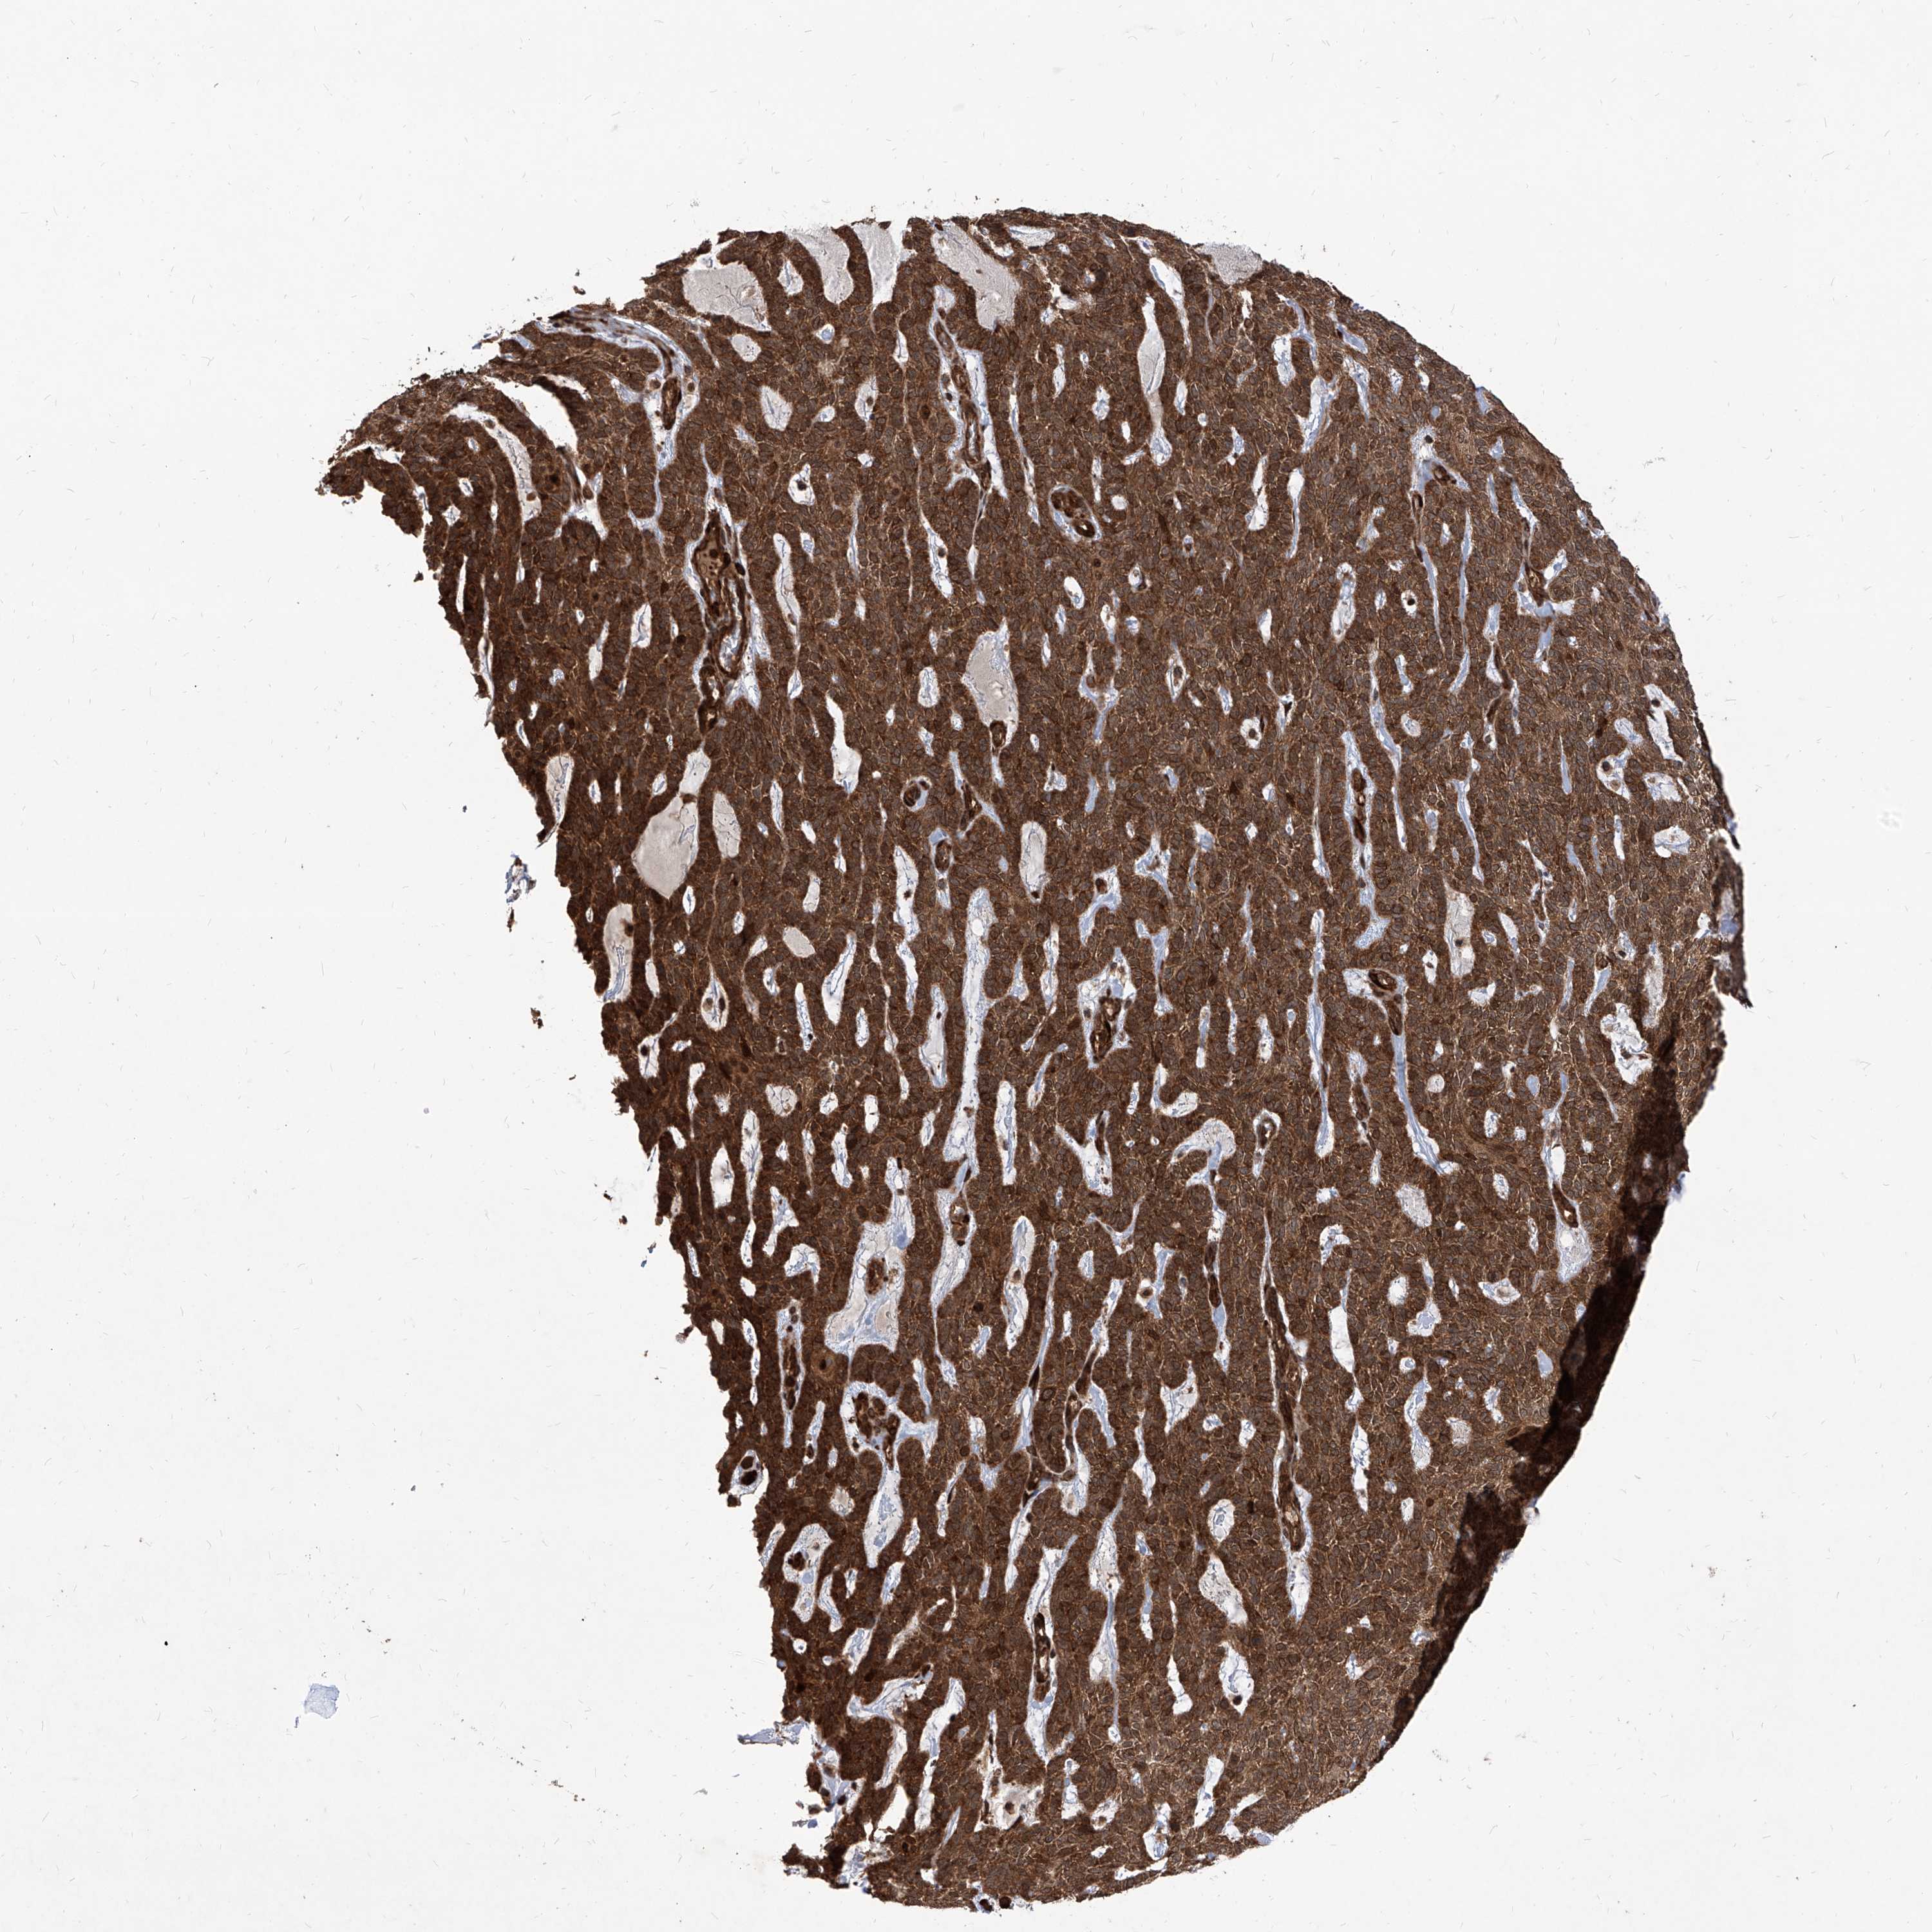

Basal cell and squamous cell cancer

SKIN CANCER - Protein expressioni

A mouse-over function shows sample information and annotation data. Click on an image to view it in a full screen mode. Samples can be filtered based on level of antibody staining by selecting one or several of the following categories: high, medium, low and not detected. The assay and annotation is described here.

Each image is clickable and will lead to virtual microscopy that enables deeper exploration of all samples and also displays staining intensity scores, fraction scores and subcellular localization as well as patient and tissue information for each sample.

Antibody HPA031572

Antibody HPA031573

Basal cell carcinoma

Squamous cell carcinoma, NOS

Squamous cell carcinoma, metastatic, NOS